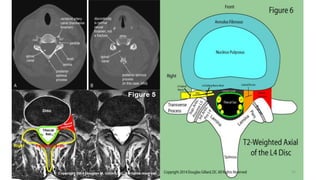

T2 sequence- Flip side of T1

•T2

• CSF, AQ/VT HUMOR WHITE

•Fat black/white mater

•Water white

•Blood vessel dark

•CSF study

•Lesions in brain